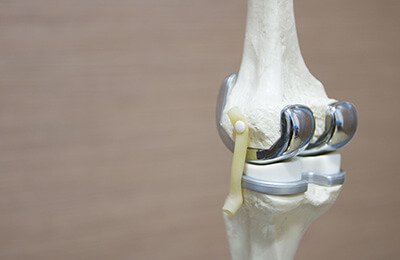

While many patients can be managed with the help of medicines, physical therapy or injections, some do not get any relief with these treatments. In such patients with advanced condition, knee replacement surgery, also called knee arthroplasty, is suggested. In this surgery, weight-bearing portion of the knee joint is replaced by an artificial structure. Today, knee replacement surgery is one of the most common bone surgeries performed around the world.